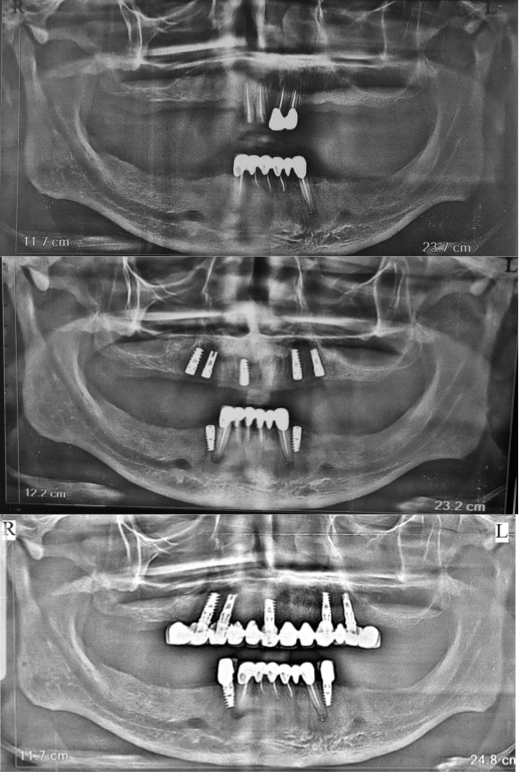

Multiple Teeth Replacement

Card image